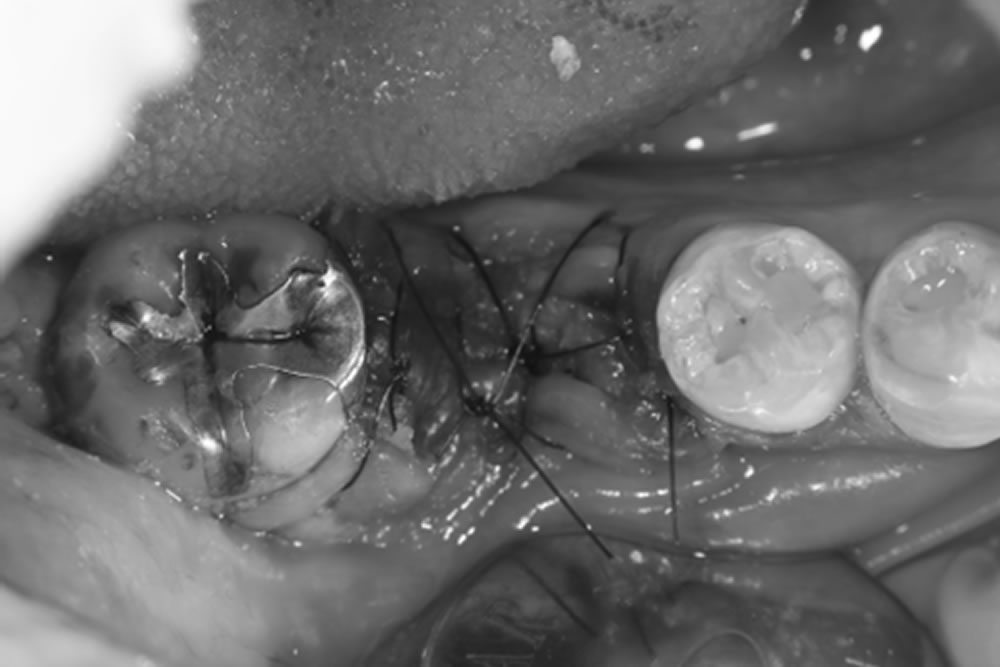

- 11.7 ⑥縫合

- 11.8 治療後の経過

治療後の経過